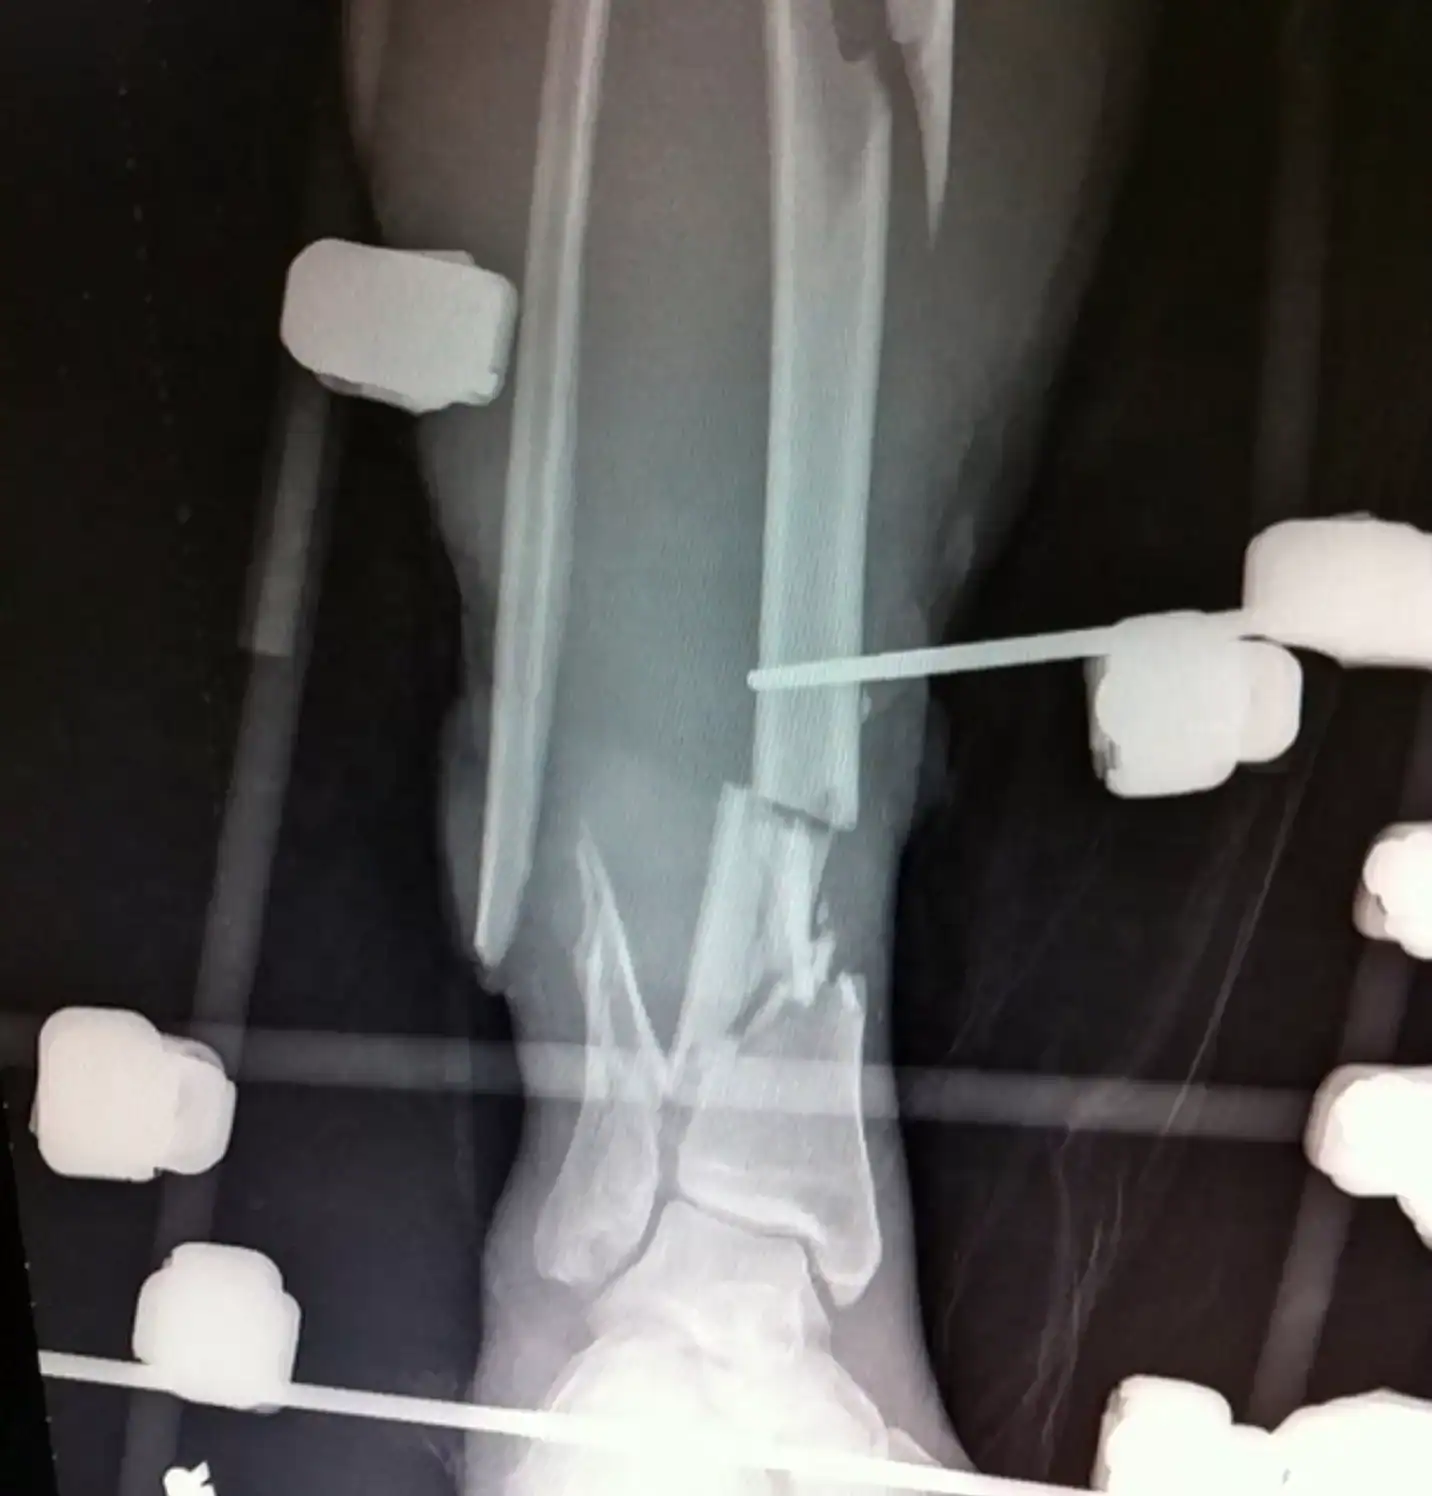

Após ser colocada em coma induzido por mais de uma semana, Amberly acordou com um ultimato dos médicos: seria necessário amputar a perna direita. “Disseram que eu tinha 1% de chance. Pensei: então você está dizendo que há uma chance. Vamos tentar salvar”, lembrou. Contra a recomendação médica, ela recusou a amputação e foi transferida para o Cedars-Sinai Medical Center, onde conheceu o cirurgião Donald Wiss, o único disposto a tentar o impossível.

O que se seguiu foram 34 cirurgias complexas ao longo de vários anos, além de um ano inteiro para reaprender a andar. “Cada cirurgia era como começar do zero. Voltava para a cadeira de rodas, para as muletas, até tentar andar de novo”, revelou.